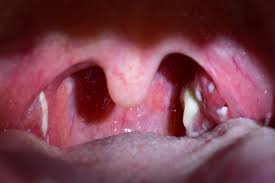

mesa de trabajo 2

Gengivitis